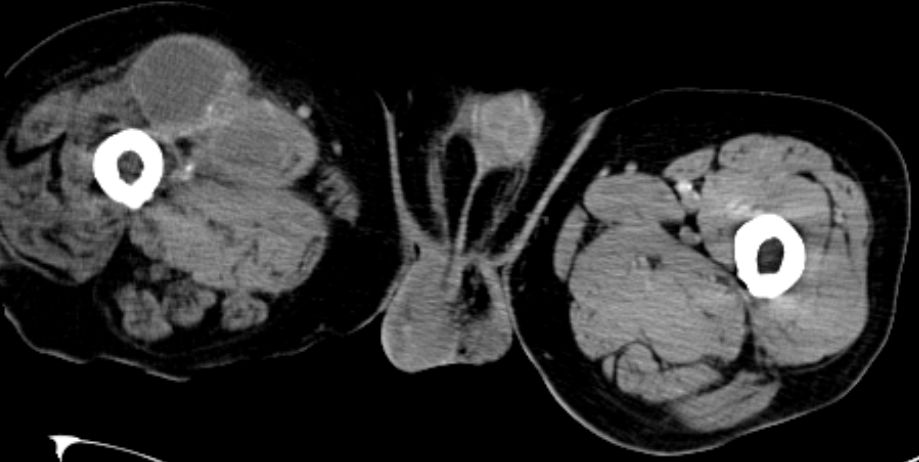

74-jähriger Mann, der vor 2 Jahren eine Beinamputation rechts wegen eines Chondrosarkoms der Tibia hatte. Jetzt ausgedehnte Knoten in der rechten Leiste. |